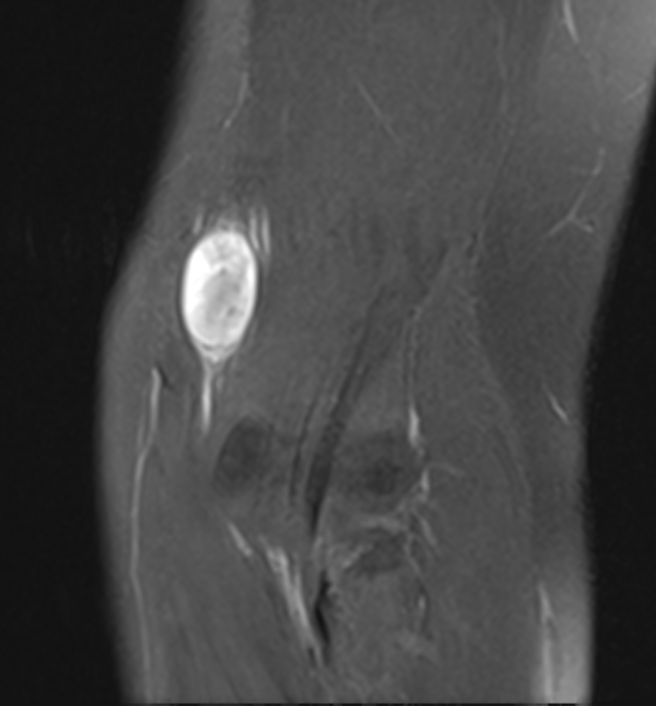

MRI

Target sign

- hypointense centrally

- hyperintense peripherally

Neurofibroma common peroneal nerve